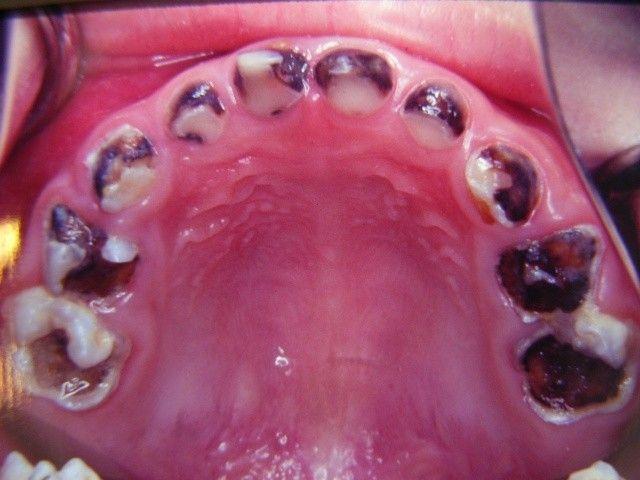

爱喝夜奶又不刷牙 4岁童 18颗牙蛀到见底 牙医也傻眼 太严重了 阿波罗新闻网

9岁女童烂牙蛀穿下巴 这个小错误你还在犯吗 宝宝树

天天一杯手搖飲牙齒蛀光光 醫生傳授一招潔牙秘訣 拯救滿口爛牙永不蛀牙 每日健康health 每日健康health

10年天天喝汽水 甜美妹牙齒 蛀黑爛光 拍片親曝慘痛下場 Ettoday國際新聞 Ettoday新聞雲

7岁男童牙齿烂光 颌骨蛀空 警惕别让自己的懒惰毁了孩子一生 快资讯